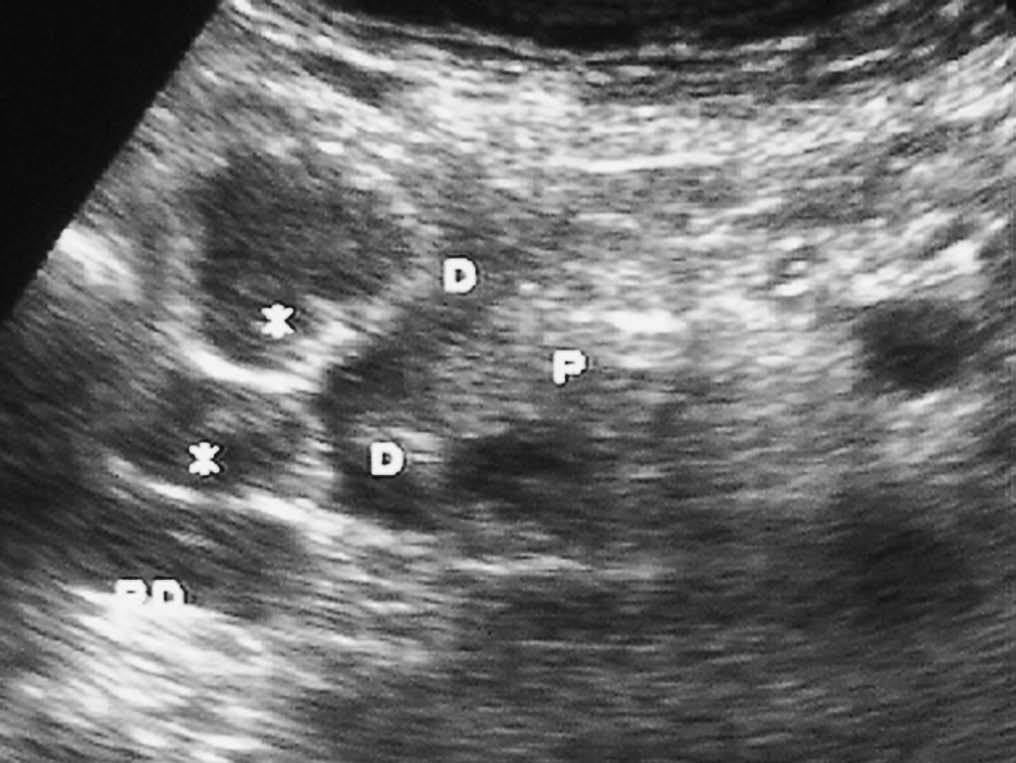

Fig. 18--Neurofibromas. (A) Ecografía. (B) Tomografía computarizada con contraste intravenoso en un paciente con enfermedad de von Recklinghausen. Se observan múltiples lesiones sólidas (*) en la pared duodenal (D). P: Páncreas.